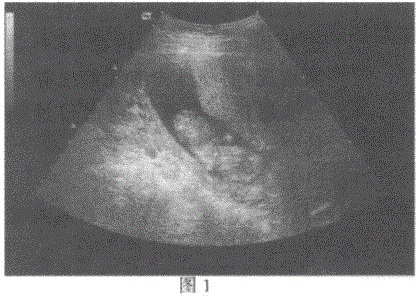

问题 临床资料:女,27岁,孕12周。 超声综合描述:图1:宫内可见8.8cm×3.2cm孕囊,内胎儿头臀长5.6cm。彩图:采用三维表面成像技术检测同一受试者,能清楚显示胎儿头面部及体表结构,请回答黄、绿箭头分别所指部位的名称: {图1} 超声提示:

选项 A.胎儿面部胎儿右上肢肘部 B.胎儿口唇胎儿肢体 C.胎儿眼睛胎儿腹部 D.胎儿鼻子胎儿肢体

答案 A